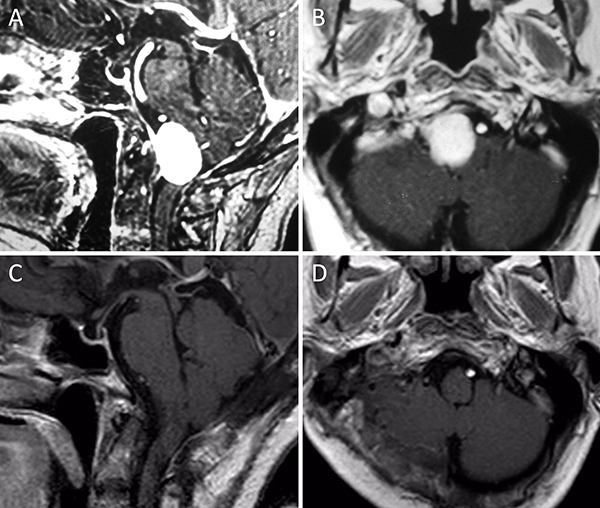

Figura 3. Meningioma clival. A-B: RM preoperatoria; C-D: RM postoperatoria.